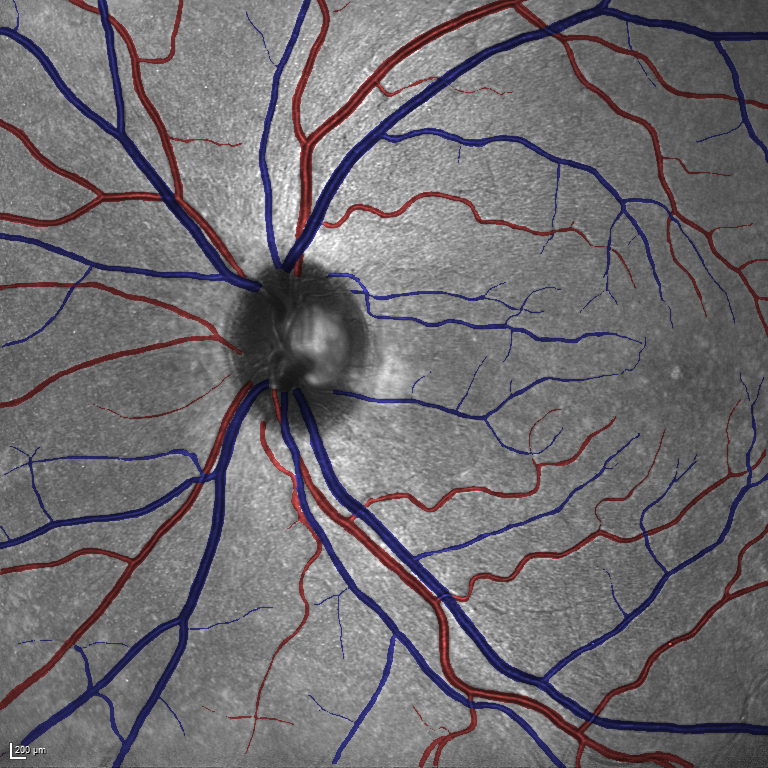

(a) Reference (b) Output (c) Width Map

As reported in Table IV, we compared the SegRAVIR model against competing deep learning-based segmentation approaches on the RAVIR dataset. Evidently, SegRAVIR outperforms these methods as judged by all metrics for artery and vein classes with a healthy margin. In terms of Dice score, SegRAVIR outperforms CE-NET, IterNet and AG-Net by , and for artery segmentation and by , and for vein segmentation, respectively. Fig. 4 presents a qualitative comparison of the semantic segmentation outputs of SegRAVIR, CE-Net, and U-Net. Specifically, SegRAVIR yields more accurate vessel topology (i.e., thickness and orientation) segmentation with higher pixel-wise classification accuracy.

Table V presents quantitative performance benchmarks of SegRAVIR and other competing approaches for retinal artery and vein classification on the RITE dataset [11]. SegRAVIR outperforms previous state-of-the-art approaches in terms of accuracy, sensitivity, and specificity. Fig. 5 provides a qualitative comparison between segmentation outputs of SegRAVIR and the method of Hemelings et al. [40] on the RITE test set.

(a) (b) (c)